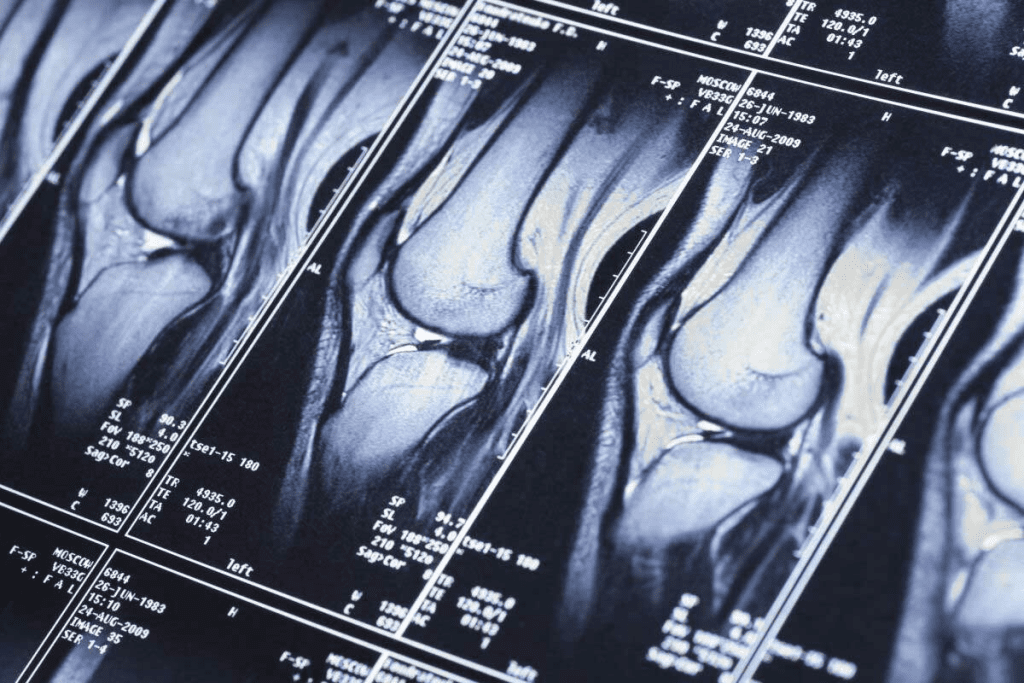

| MRI | Provides high-resolution images of soft tissue and bone marrow | Useful for evaluating spinal cord compression and soft tissue involvement |